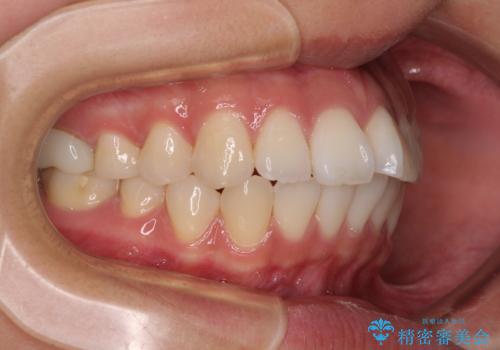

- 前歯が突出して、眠るときに口が開いてしまうことを気にして来院された患者様です。

横から見た際の口元の飛び出した印象も改善したいとのことで、上下左右の第一小臼歯4本を抜歯し、ワイヤー装置にて抜歯矯正を行うこととしました。